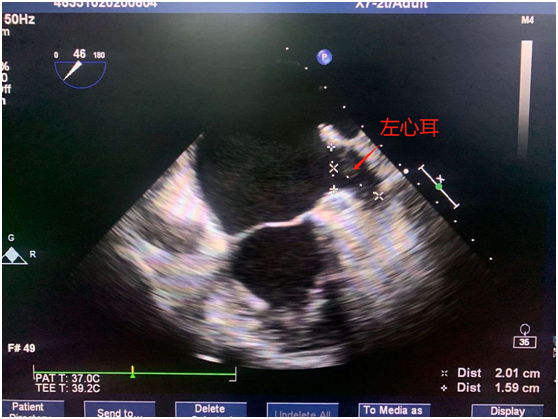

術前心臟超聲左心耳示意圖

72歲的蔣伯伯有多年心房顫動病史,就在5月初,蔣伯伯發生了急性腦栓塞,在我院神經內科行腦血管造影+取栓術,此次復查食道超聲仍然發現其心耳存在明顯云霧影,將來再次發生腦栓塞的風險極高,在黎榮山副院長、心血管內科卓柳安副主任的帶領下,我院心血管內科心電生理介入團隊與結構性心臟病介入團隊共同協作,在超聲科、麻醉科、介入室的協助下為蔣伯伯成功實施了射頻消融+左心耳封堵“一站式”手術,解決其房顫帶來的困擾。